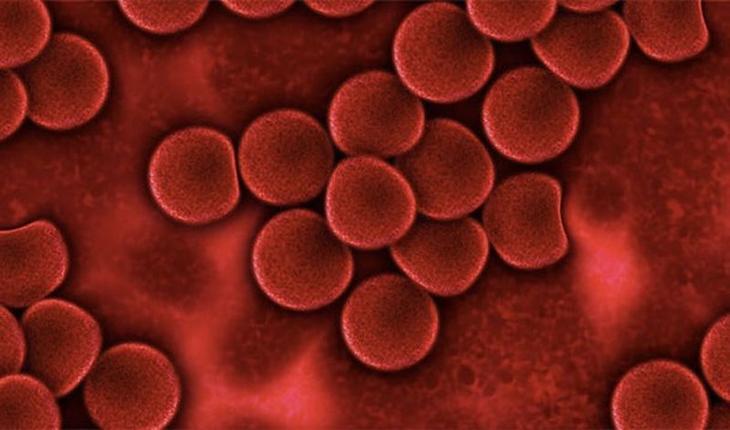

6) Кровеносная система тоже отличается у представителей разных полов. Так, у мужчин в крови больше эритроцитов и меньше воды, а у женщин процент эритроцитов на 20% ниже чем у мужчин, в то время как воды в крови у женщин содержится больше. Кроме того, по мужскому организму кровь циркулирует достаточно равномерно, а у женщин циркуляция, а, следовательно, и концентрация крови значительно выше в области таза и жизненно важных органов.